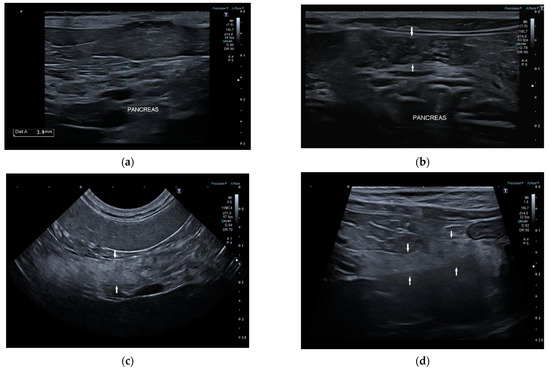

Ultrasonographic Findings of Exocrine Pancreatic Insufficiency in Dogs

by Tina Pelligra, Caterina Puccinelli, Veronica Marchetti and Simonetta Citi

Vet. Sci. 2022, 9(8), 407; https://doi.org/10.3390/vetsci9080407 - 4 Aug 2022

Exocrine pancreatic insufficiency (EPI) is a syndrome characterized by insufficient synthesis of pancreatic enzymes leading to clinical symptoms of malabsorption and maldigestion. There are no studies about ultrasonographic appearance of the pancreas with EPI in dogs. The purpose of this retrospective study was [...] Read more.

Exocrine pancreatic insufficiency (EPI) is a syndrome characterized by insufficient synthesis of pancreatic enzymes leading to clinical symptoms of malabsorption and maldigestion. There are no studies about ultrasonographic appearance of the pancreas with EPI in dogs. The purpose of this retrospective study was to describe ultrasound features of the pancreas during EPI in this species. Dogs with history and clinical signs of maldigestion, serum canine trypsin-like immunoreactivity (cTLI) values <5 µg/L, and abdominal ultrasound exam were included in the study. Size, shape, margin, echogenicity, echostructure, and pancreatic duct appearance of the right pancreatic lobe were valued. Additional sonographic intestinal findings were recorded. Thirty-four dogs were included. The mean pancreatic thickness in our population was significantly lower than the mean reference values of healthy dogs. In 68% of dogs, the pancreas had a normal ultrasound appearance. Ultrasonographic intestinal abnormal findings were identified in 85% of dogs and were suggestive of inflammatory bowel disease. Despite the fact that EPI is a functional diagnosis, ultrasound evaluation should be considered among the useful tests. The finding of a normal but thinned pancreas associated with sonographic intestinal signs of inflammatory bowel disease in dogs with typical history and supportive clinical signs could suggest a diagnosis of EPI. Full article

Show Figures

Figure 1